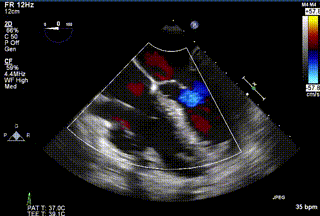

2021年12月24日,復(fù)旦大學(xué)附屬中山醫(yī)院葛均波院士團隊成功應(yīng)用LuX-Valve Plus為一例極重度三尖瓣反流(TR)合并房顫、房缺的患者完成了經(jīng)血管三尖瓣置換術(shù),這是在前基礎(chǔ)上,本周完成的第三例經(jīng)血管三尖瓣置換手術(shù),葛均波院士、周達(dá)新教授等與心外科魏來教授、賴顥教授,心超室的潘翠珍教授、李偉教授及麻醉科的郭克芳教授共同完成了本周手術(shù),均獲得圓滿成功!患者術(shù)后超聲顯示無TR,臨床癥狀明顯改善。本周手術(shù)的成功也為LuX-Valve Plus救治性臨床研究添上了濃墨重彩的一筆。

三例患者入院后,葛均波院士團隊周達(dá)新教授、潘文志教授、張源博士、陳莎莎博士及心超室的潘翠珍教授、李偉教授對患者的情況進(jìn)行詳細(xì)評估和討論,最終決定為三例患者選擇LuX-Valve Plus40mm、50mm和50mm型號的瓣膜進(jìn)行手術(shù)治療。手術(shù)后即刻拔除氣管插管,術(shù)后患者三尖瓣反流癥狀得到顯著改善,復(fù)查心超結(jié)果顯示人工三尖瓣瓣膜支架固定穩(wěn)定,瓣葉關(guān)閉形態(tài)未見異常,未見明顯反流。